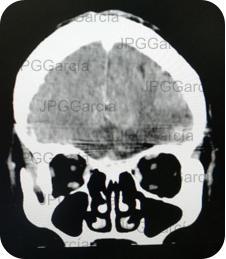

Tumor del plano esfenoidal clasificado por imagen como Meningioma visto a través de resonancia magnética cortes axial y coronal